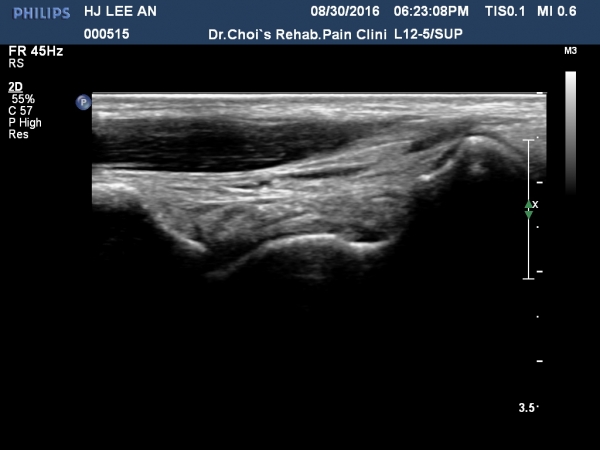

ÃÊÀ½ÆÄ °Ë»ç

¹ß¸ñ ¾ÕÂÊ Á¾´Ü¸é°Ë»ç¿¡¼­ °üÀý³» ¼ö¾×Àú·ù´Â ¶Ñ·ÈÇÏÁö ¾ÊÀ¸³ª °æ°ñ °Å°ñ Á¢Ã˺ο¡ ¼Ò·®ÀÇ

¼ö¾×Àú·ù°¡ °üÂûµÊ(»çÁø 1, 2).